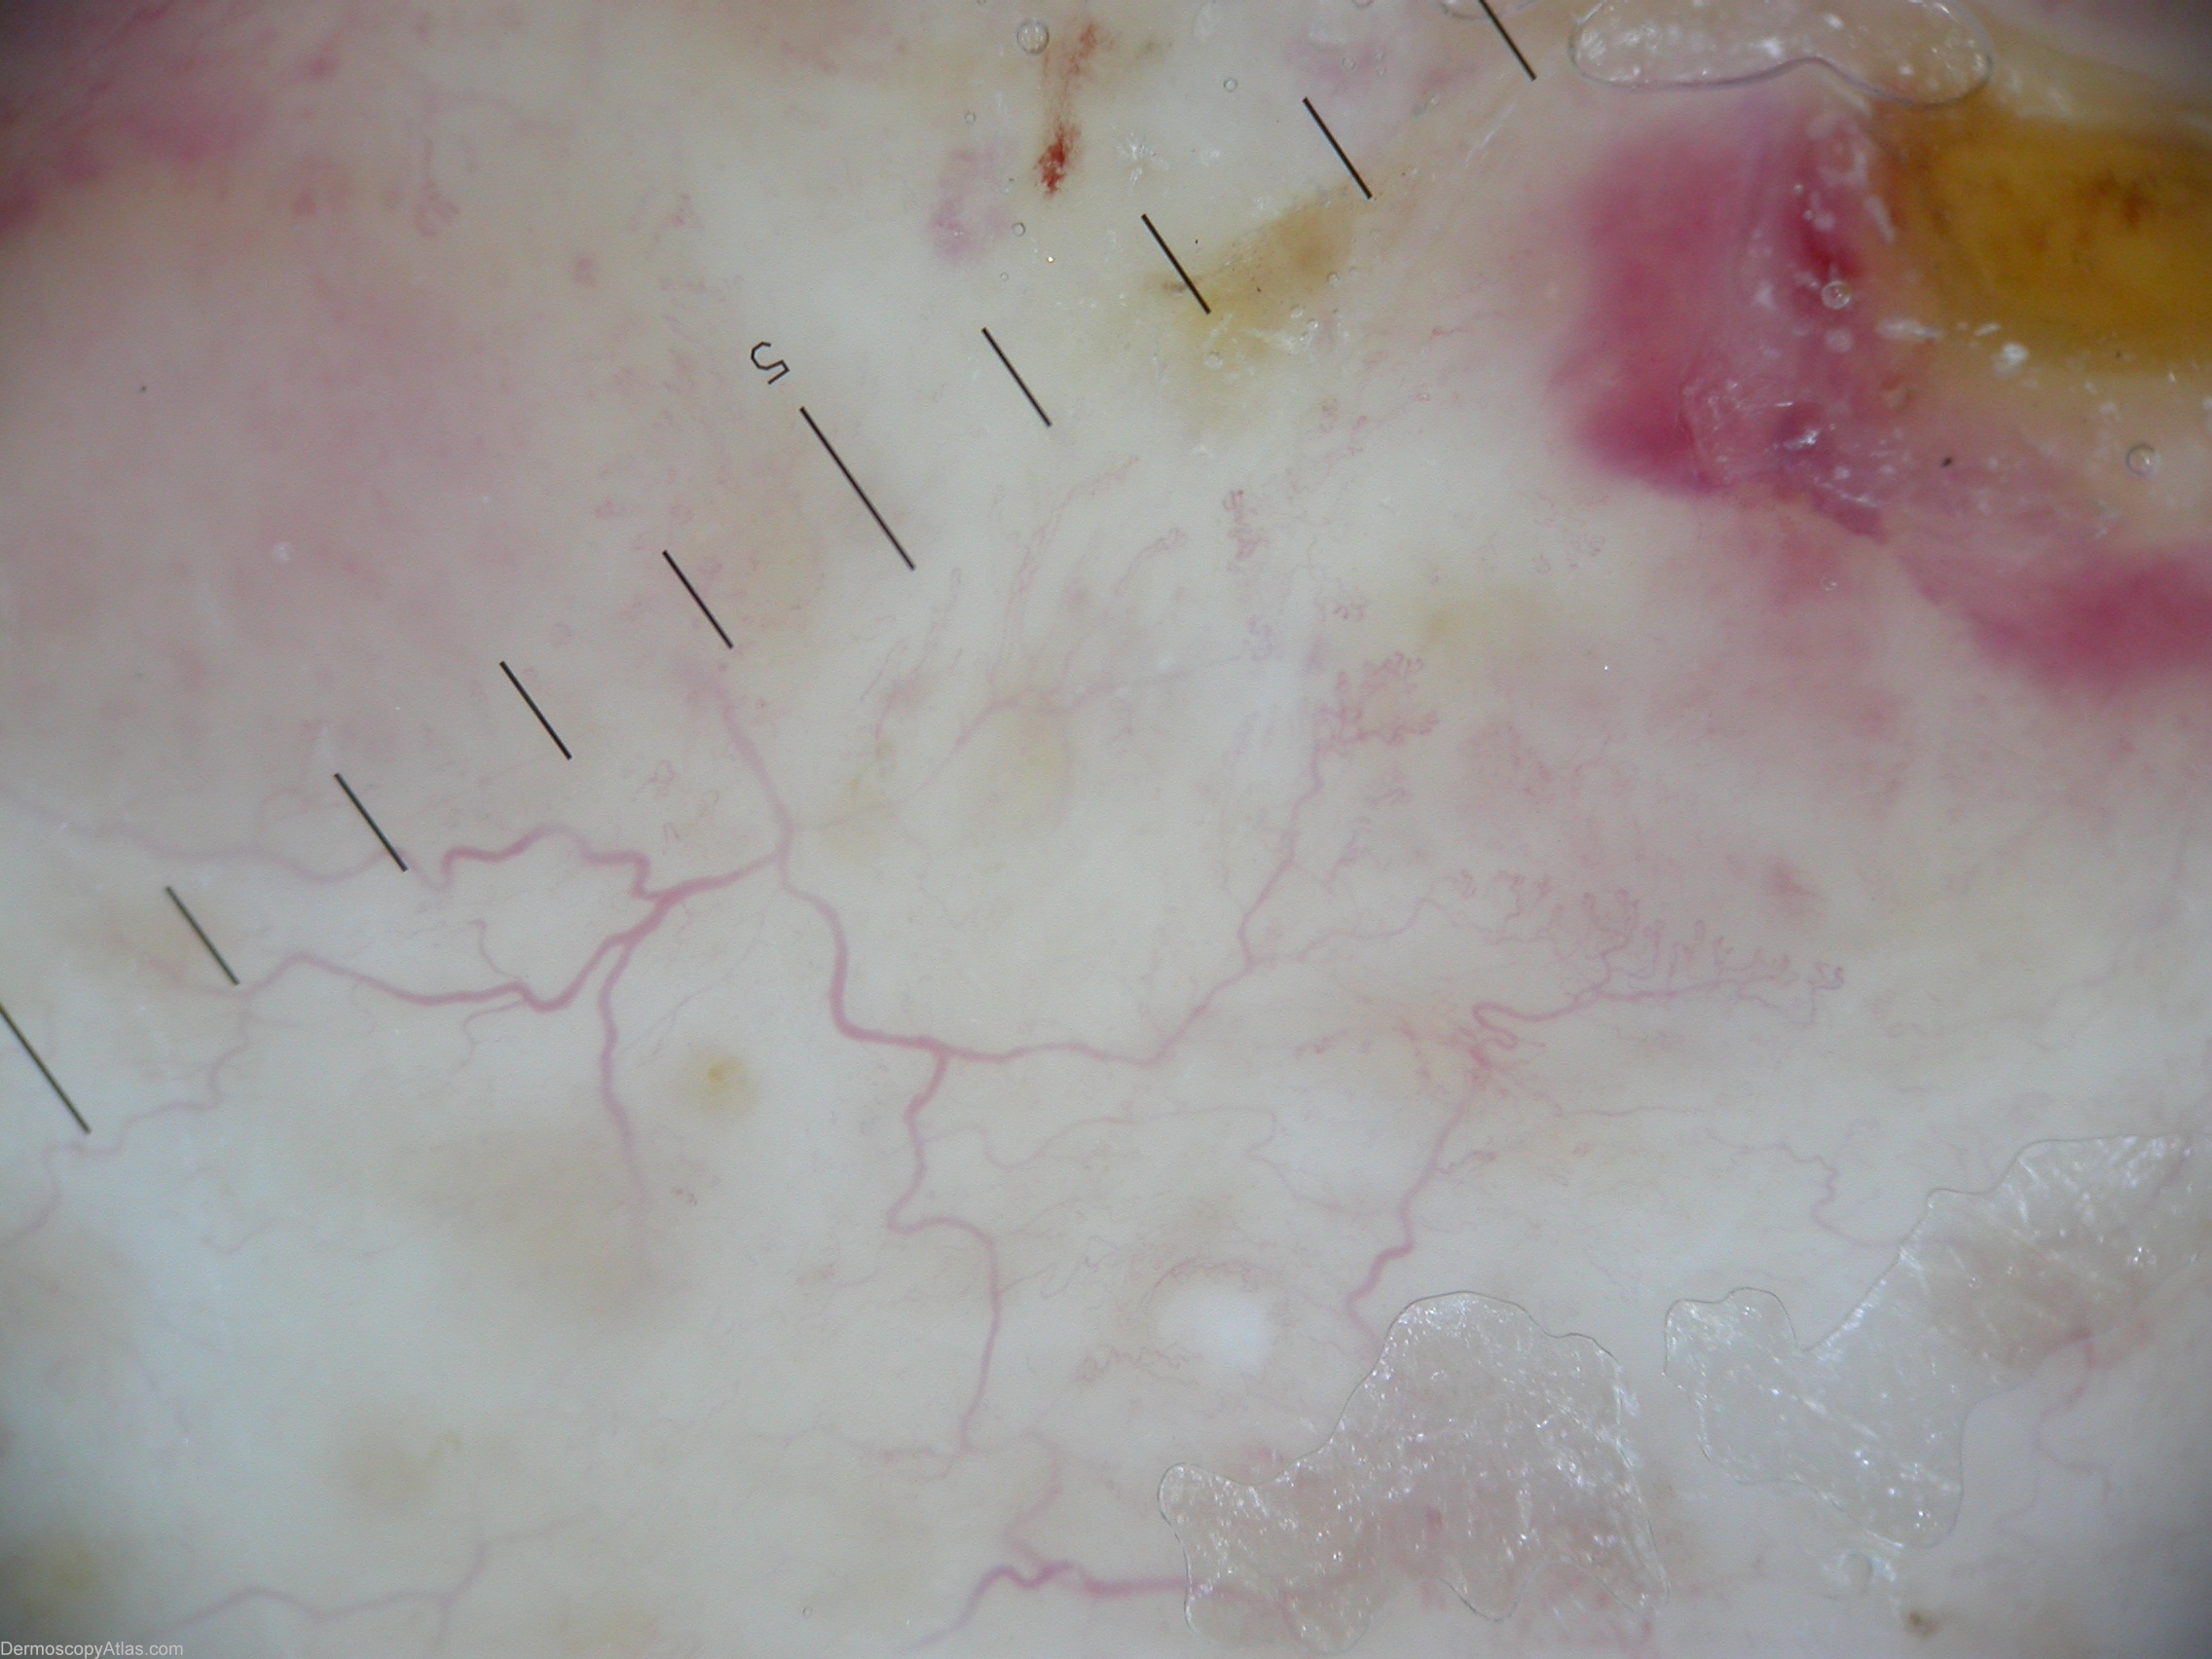

Diagnosis: Necrobiosis lipoidica

Description: Accentuated arborizing vessels with pearl-white areas of fibrosis.

History: This plaque continued to expand slowly one year after it appeared on the shin of a 49 year old nondiabetic woman. A biopsy showed altered collagen and granulomatous inflammation typical of necrobiosis lipoidica. Dermascopic picture of necrobiosis lipoidica could be described by accentuated arborizing vessels with pearl-white areas of fibrosis.